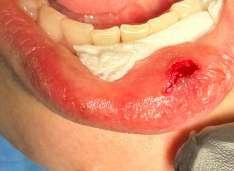

Il mucocele del cavo orale è la seconda lesione più comune. Nella fascia di età compresa tra 10 e 29 anni, il tasso di incidenza è più elevato. Il mucocele è caratterizzato da un accumulo di mucine. Ha una forma a cupola. Di solito hanno un colore bluastro. Il

mucocele si trova più comunemente sul labbro inferiore, seguito dalla mucosa buccale e dal pavimento della bocca. L'incisione tradizionale con bisturi e/o l'escissione chirurgica, la marsupializzazione, la micromarsupializzazione, l'iniezione di corticosteroidi, l'agente sclerosante, la criochirurgia, l'elettrochirurgia e il laser sono tutte procedure validate per il trattamento del mucocele in letteratura.

Questo caso è coerente con precedenti segnalazioni di escissione del mucocele utilizzando un laser a diodi.

L'enorme quantità di tessuto rimosso e il livello di comfort del paziente supportano ulteriormente il fatto innovativo che può essere utilizzato anche per il mucocele di grandi dimensioni.

I mucoceli della mucosa orale sono malattie tumorali benigne delle ghiandole salivari minori della mucosa orale. Si verificano più comunemente nella mucosa labiale. Possono essere causate da una rottura dell'epitelio della ghiandola che secerne saliva nello spazio extraghiandolare e forma una pseudocisti (mucoceli da stravaso) oppure da un blocco del flusso salivare dovuto ad una proliferazione epiteliale del dotto escretore che forma una cisti salivare (cisti da ritenzione).